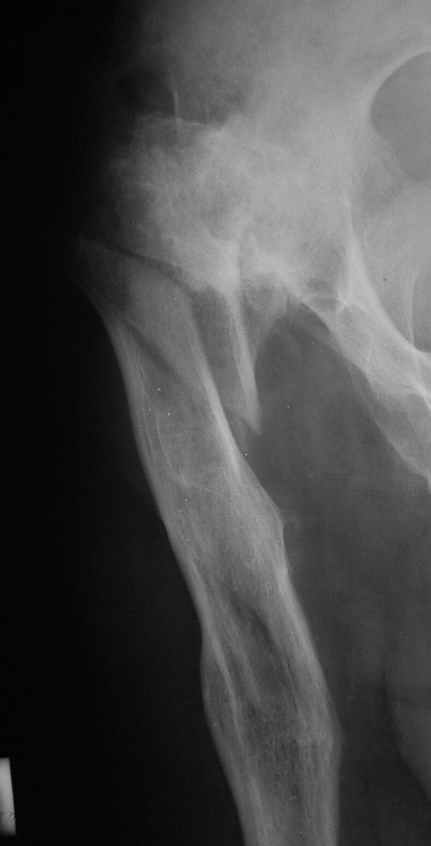

Рентгенограммы до и после. Больной профессор на кафедре сопромата и после детального изучения

особенностей имплантата, собственных рентгенограмм дал добро на операцию. Ваш вариант лечения вполне симпатичен.